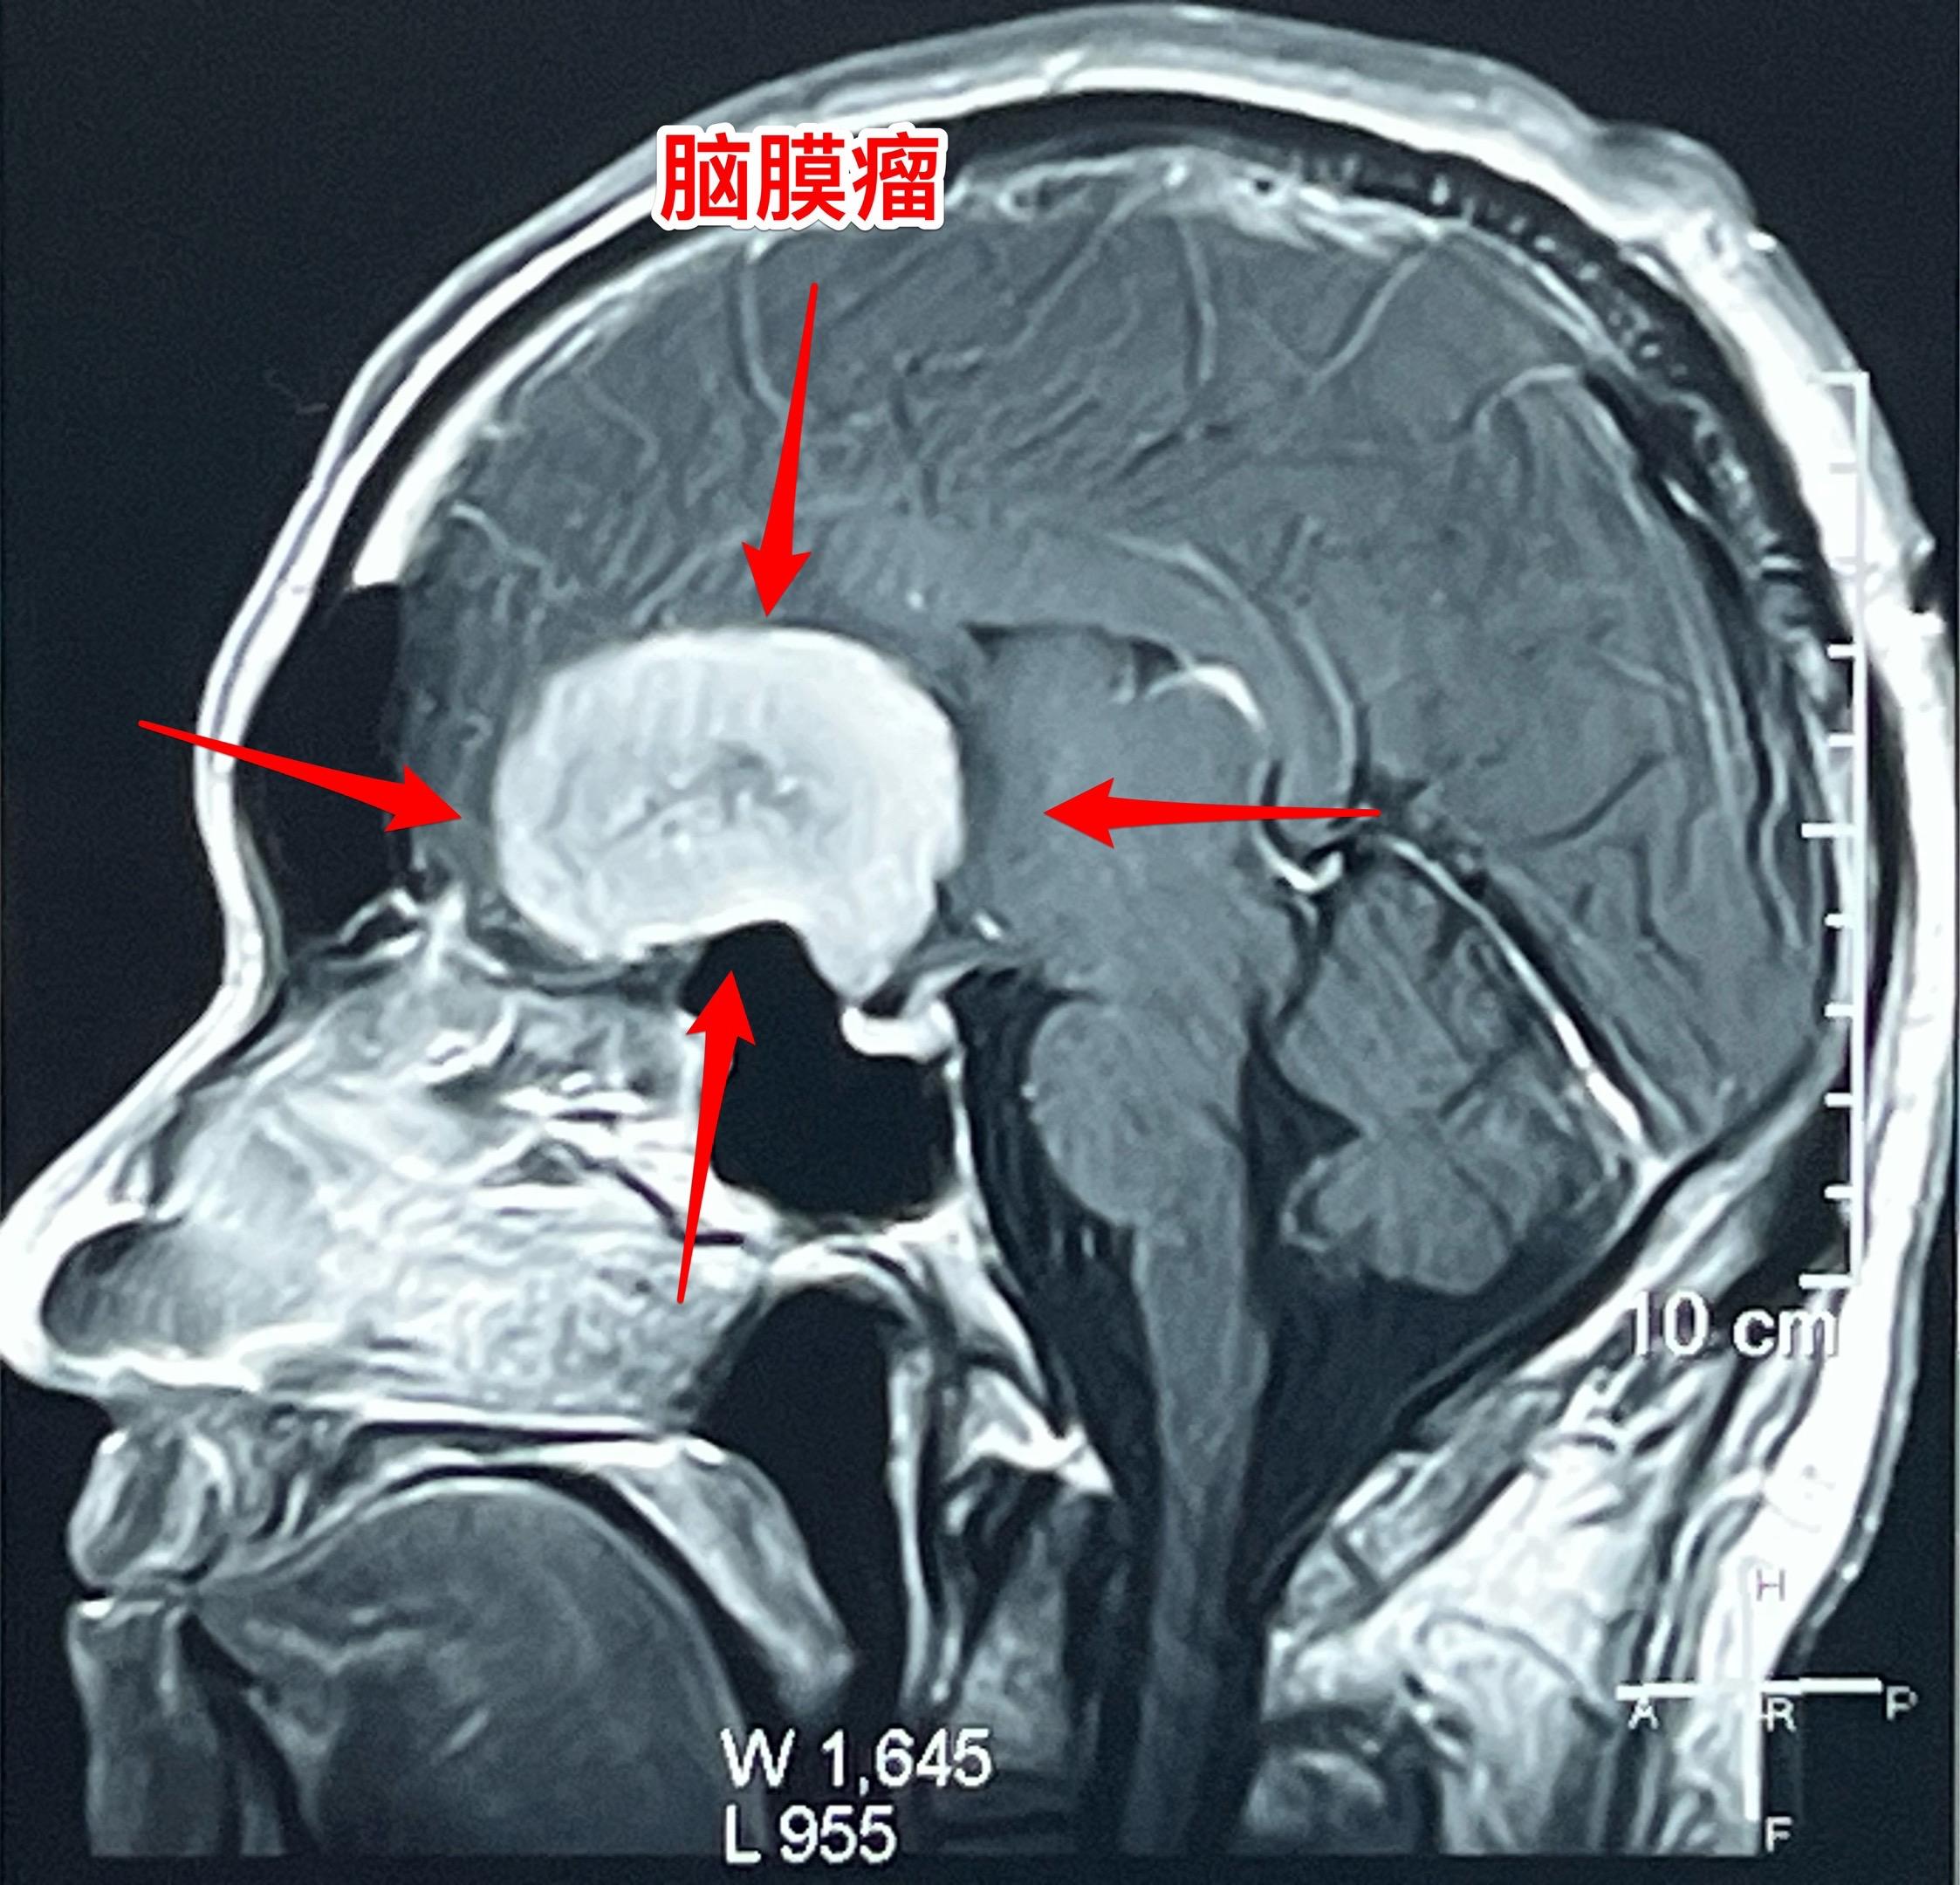

脑膜瘤长在不同的部位产生的症状也不同!这个59岁的内蒙古男性,最开始的症状是右眼视力下降,他认为与糖尿病有关,没有作详细检查。今年出现头痛症状,后来又出现左腿无力症状,他自认为是脑梗塞。症状越来越严重,还发现了嗅觉丧失症状。医生建议行脑部磁共振检查,作了磁共振之后就发现了这个巨大肿瘤。 这个脑膜瘤位置靠近嗅神经、视神经,所以导致视力下降和嗅觉丧失,同时肿瘤导致右侧大面积的脑水肿,造成左腿无力。手术后这些症状有望好转。